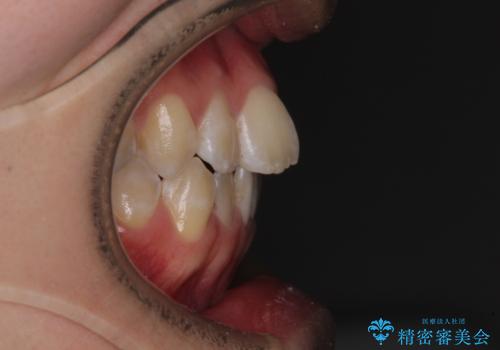

- 上下前歯のデコボコを気にして来院された患者様です。

ワイヤー矯正でもマウスピース矯正でも可能でしたが、短期間で、自身の手を煩わせることなく治療を行いたいとのことで、ワイヤー装置にて矯正治療を行うこととしました。